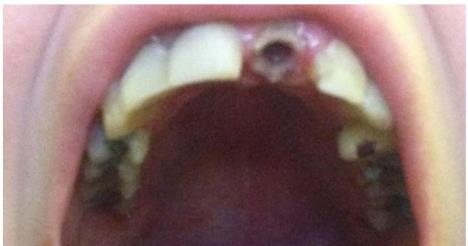

Imala je i urgentni zahvat da ukloni nerve. Posle toga kaže, njeni zubi su počeli da se raspadaju.

"Sedela sam i gledala TV i sećam se da sam osetila kako mi se zub raspada u ustima", priseća se.

"Nisam znala šta da radim, samo sam počela da plačem. Lice je počelo da mi otiče zbog nakupljanja tečnosti. Bilo je jezivo."

Otišla je kod zubara koji joj je izbušio rupe u zubima da bi izbacio tečnost, ali zub je nastavio da se kruni.